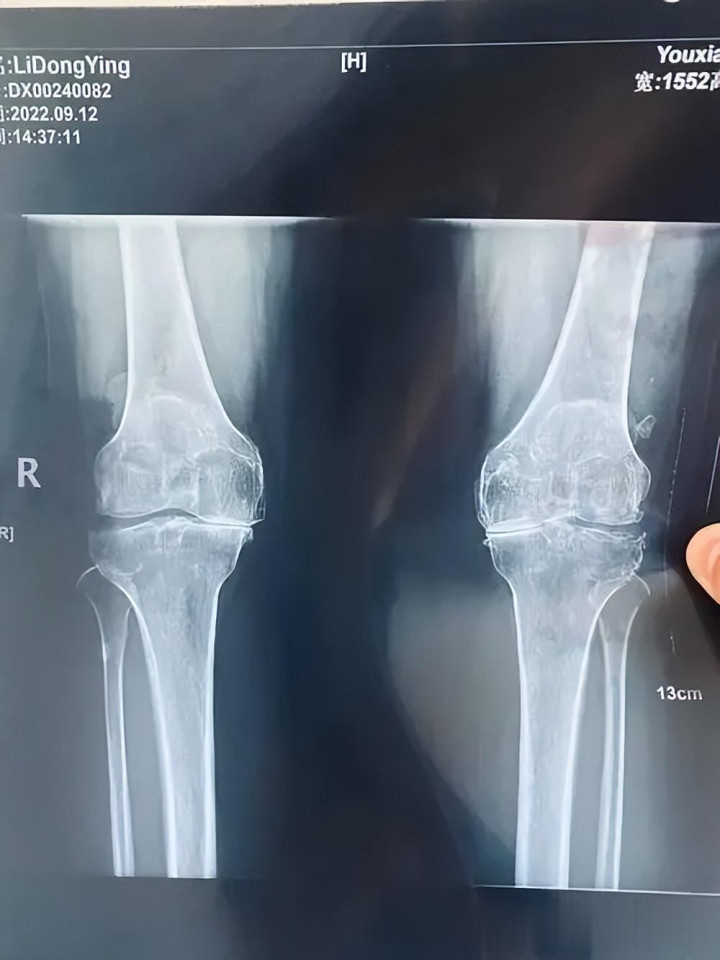

我旧地的邻居,找我看病的时候或者是89岁。右膝关键凄沧肿胀,也曾不可下床行走,卧床一个月了。周末我回家的时候,他男儿把我叫到她家去的,在路上给我先容了老夫人的病情。普通右膝关键就凄沧,在隔壁诊所口服麻醉剂诊治(具体省略,我辩论是麻醉剂和激素药),2个月前瞬息严重了,在隔壁病院拿了口服药,局部打了针,抽了积液,贴了膏药。咫尺吃药吃的胃痛,贴膏药局部痒。见到老夫人,我表现她减弱,逐渐诉说病情,同期仔细为她作念了身体搜检——按压膝关键周围,有理解压痛,浮髌磨练阳性,屈伸时能听到轻微的骨擦音,王人集她底本的X线片,明确会诊为老年女性膝关键骨性关键炎兼并滑膜炎。

王人集老夫人的年岁、病史和体质,我先耐烦为她和家属解读病情:老年女性绝经后,雌激素水平下落,膝关键软骨失去保护,再加上始终劳累、寒湿入侵,导致软骨磨损退化,滑膜受到刺激后分泌过多积液,进而激勉肿胀、凄沧、僵硬,这在中医领域属于“痹证”,中枢病机是肝肾不及、寒湿瘀滞、经络欠亨,“通则不痛,痛则欠亨”,诊治的关键的是温通经络、收场寒湿、活血化瘀、滋补滑膜,同期保护关键软骨,缓解症状、减速推崇。